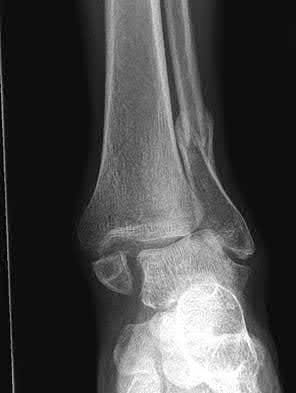

Figure A is an AP radiograph of a posterior knee dislocation. Figure B is a lateral showing the same injury.